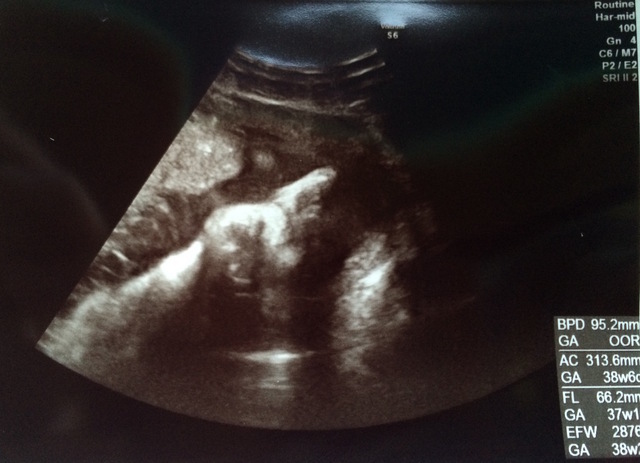

37週2日(37w2d・男の子)|homiho さん(27歳)

エコー写真撮影時のエピソード:

臨月に入ってお腹が重くて何をするのも大変でした。でもお腹の中で元気に暴れまわってるのを感じると、痛みよりももうすぐ会えるんだなーとか胎動を感じられるのもあと少しなんだなーとわくわくして毎日を過ごしていました。この時のエコー写真で初めて正面の顔を見ることができて、パパとあまりにもそっくりだったので両家の家族や共通の友達と大笑いしたのを覚えています。この時点で推定体重が3200gになっていて、初めての出産でこんなに大きい子を無事に普通分娩で産めるのか不安でしたし、体を動かすのは大変な時期でしたが家族に支えられて楽しく毎日を過ごしていました。